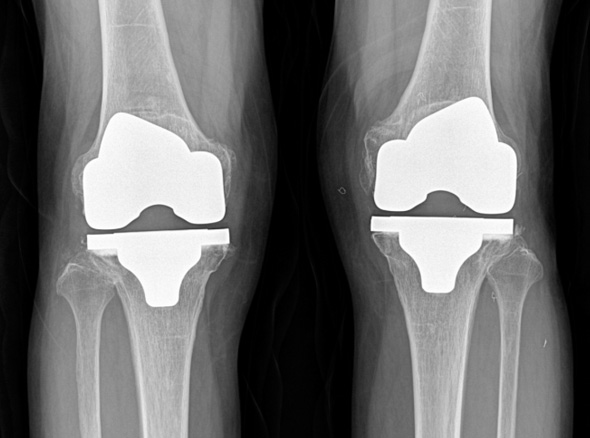

손상된 무릎 뼈를 제거하고, 그 부위에 특수 소재의 금속 재질로 구성된 인공관절을 삽입하는 수술을 시행할 수 있습니다.

관절연골이 망가져 쓸 수 없을 때 관절기능 회복을 위해 시행하며, 인공관절의 수명은 20~30년 정도 됩니다.

세계적인 의료기기 기업 스트라이커(Stryker)사의 특화된 임플란트를 사용합니다.

정밀한 설계, 내구성, 생체 적합성 등의 장점을 두루 갖추어 전 세계적으로 가장 많이 사용되고 있습니다.

최대한 가볍고 오래 사용 가능하며 알러지를 거의 유발하지 않는 인공관절을 사용합니다.